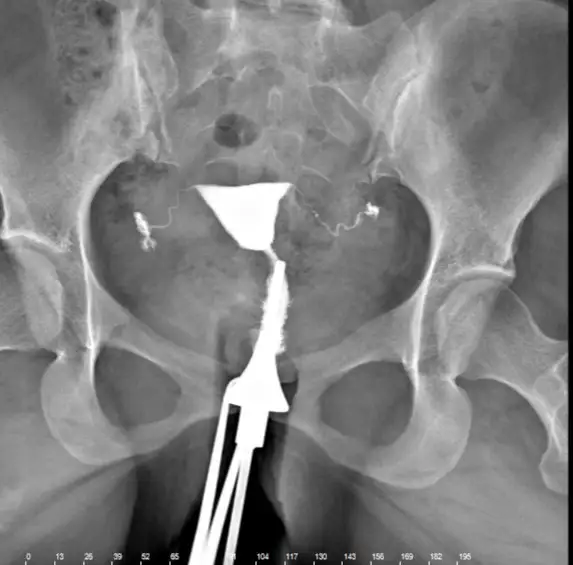

Kızlar rahim filmi sonrası doktor arka arkaya hasta alıyordu herşey yolunda dedi çıktım perde var mı Y ya da kalp şeklinde gibi riskli durum var mı soramadım anlayanlar bakabilir mi bir sorun gören var mı?

Ay tüplere bak saç teli gibi ne kadar ince yaaaKızlar rahim filmi sonrası doktor arka arkaya hasta alıyordu herşey yolunda dedi çıktım perde var mı Y ya da kalp şeklinde gibi riskli durum var mı soramadım anlayanlar bakabilir mi bir sorun gören var mı?

Biri tıkalı idi üç kere basınç tazzik ile açtı doktor sağ olsun canım umarım tıkanmamıştır tekrar peki canım rahim iyi mi sence y şeklinde kalp şeklinde falan değil demi ya da perdeli?Gayet güzel tüplerin de açık canım

Biri tıkalı idi üç kere basınç tazzik ile açtı doktor sağ olsun canım umarım tıkanmamıştır tekrar peki canım rahim iyi mi sence y şeklinde kalp şeklinde falan değil demi ya da perdeli?

Doktor arka arkaya hasta alıyordu canım hiç soramadım ondan dört ay oldu unuttum şimdi aklıma gelmişken size sorayım dedim inşalah tüpler tıkanmamıştır dört ay oldu beş ay olacak çektireli o zaman biri tıkalı idi üç sefer basınç ile açtı doktor inşalah tıkanmamıştır. Sen de öyle düşünme Rabbim ol derse her şekilde olurYok canım gayet normal sen benimkini görsen kendinin normal olduğunu anlarsın :))

Doktor arka arkaya hasta alıyordu canım hiç soramadım ondan dört ay oldu unuttum şimdi aklıma gelmişken size sorayım dedim inşalah tüpler tıkanmamıştır dört ay oldu beş ay olacak çektireli o zaman biri tıkalı idi üç sefer basınç ile açtı doktor inşalah tıkanmamıştır. Sen de öyle düşünme Rabbim ol derse her şekilde olur ❤